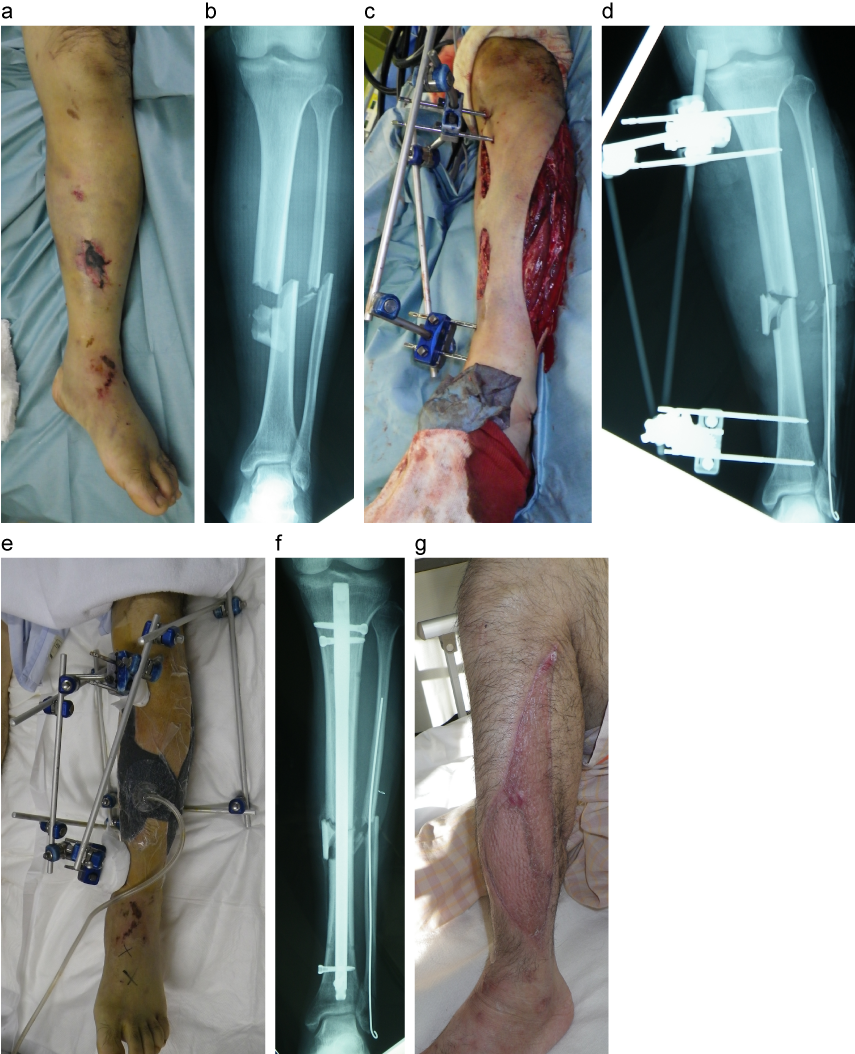

典型例(66歳男性)の所見

a:来院時外表所見

b:来院時単純X線所見正面像

c:緊急手術後外表所見(洗浄デブリドマン、減張切開、創外固定術)

d:緊急手術後単純X線所見正面像

e:陰圧持続吸引

f:最終内固定後単純X線所見正面像

g:最終外表所見